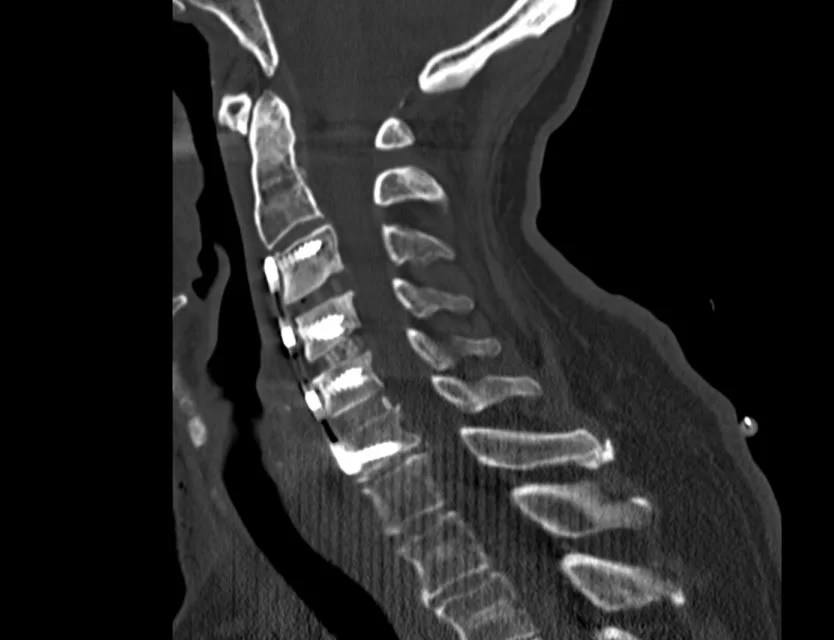

Η σπονδυλοδεσία μπορεί να εφαρμοστεί τόσο στην αυχενική μοίρα όσο και στην οσφυϊκή μοίρα της σπονδυλικής στήλης. Στη θωρακική μοίρα είναι λιγότερο συχνή η ανάγκη σπονδυλοδεσίας, λόγω της σταθερότητας που προσφέρει ο θωρακικός κλωβός (θώρακας).

Η προσπέλαση μπορεί να είναι πρόσθια (δηλαδή από μπροστά, όπως πχ. συχνά στον αυχένα, Εικόνα 2), οπίσθια (όπως πχ. συχνά στη μέση, Εικόνα 3) ή και πλάγια (όπως πχ. σε τεχνικές όπως το XLIF κλπ.)